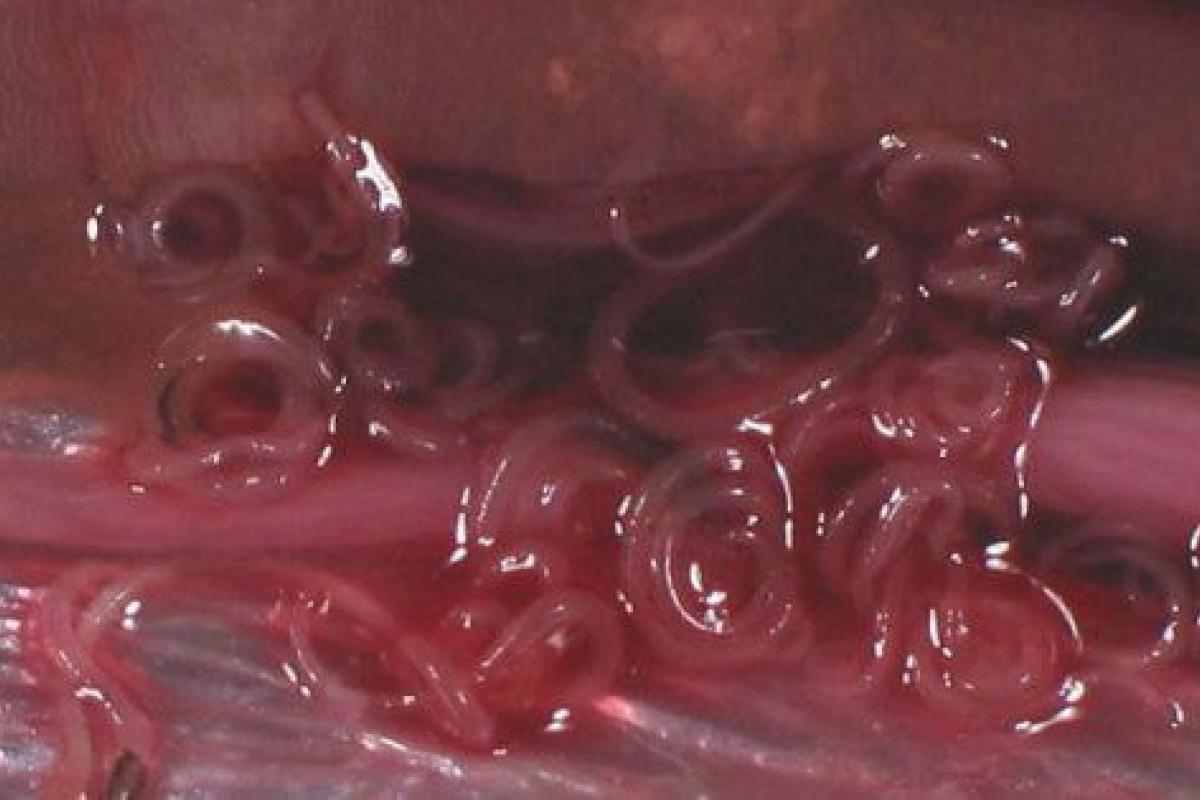

España se sitúa después de Japón como el país con mayor número de intoxicaciones por anisakis, un parásito que se transmite a los seres humanos a través de la ingestión de pescados o cefalópodos contaminados y que provoca trastornos gastrointestinales y alérgicos.

Uno de cada tres pescados que se consumen en España está infectado

Uno de cada tres pescados que se consumen en España está infectado. Se producen 8.000 casos al año, sobre todo en Euskadi, Madrid, Cantabria y Andalucía.

Si bien el porcentaje de muestras afectadas es muy variable según la zona de origen y la época del año, los pescados más frecuentemente parasitados son la merluza y el bonito, pero los boquerones y anchoas provocan más intoxicaciones en España.